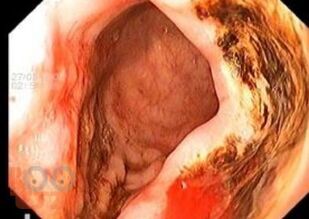

В первой части учебного пособия «Осложнения язвенной болезни желудка и двенадцатиперстной кишки» отражены современные представления об этиопатогенезе язвенной болезни желудка и двенадцатиперстной кишки. Подробно изложены классификация, клиническая картина, современные методы диагностики и лечения перфоративной язвы желудка и двенадцатиперстной кишки. Особый акцент сделан на принципах предоперационной подготовки, выборе метода хирургического лечения и послеоперационном ведении больных с данной патологией.